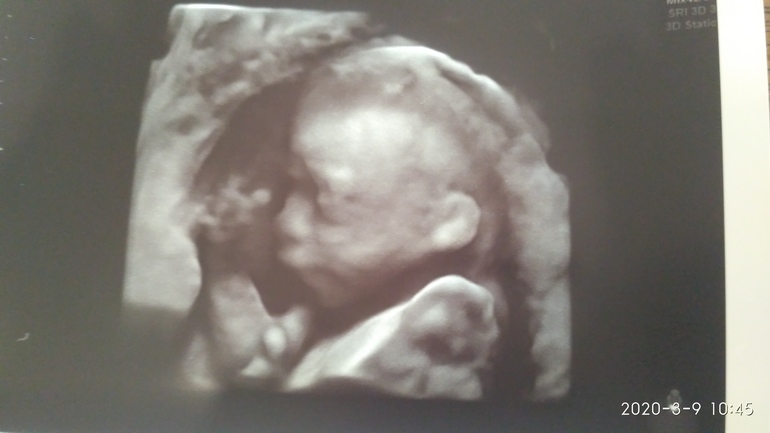

Второй скрининг и... Мальчик))

БеременностьНу уж как все были уверены, что девочка! Ждали девочку! Надеялись на девочку. А на скрининге сказали, что однозначно мальчик. Наш папа прям там чуть не расплакался))) Потом меня выгнали посидеть или погулять по коридору, потому что ребёнок лежал так, что один из срезов сердца было невидно. Мы вышли в коридор, сели на диванчик и стали выбирать имя с буквой "Л". Поржали от души😂. От Пантелеймона до Лавра прошлись и попримеряли, потом муж сказал, что, кажется, нашёл идеальное для нас: "Гореслав!" Шикарно, конечно😆.

Выходя из клиники, уже смирились с мальчиком. Тем более, он такой хорошенький😇. Пока остановились на имени Олег. По-моему, Олег Григорьевич звучит хорошо.

Лапусик какой. Нам на 2 скрининге не сделали фото. Зато на 3ем в платной оторвались на фотках. Легеой беременности и родов в срок))

Ага)) Смотрю на него, прям совсем человечек готовый! Даже в голове не укладывается, что в нём всего 350 граммов))

Дааа, уже человек)) не подумать, что 350 грамм. Жду своего второго скрининга)) до конца месяца время будет тянуться очень долго...